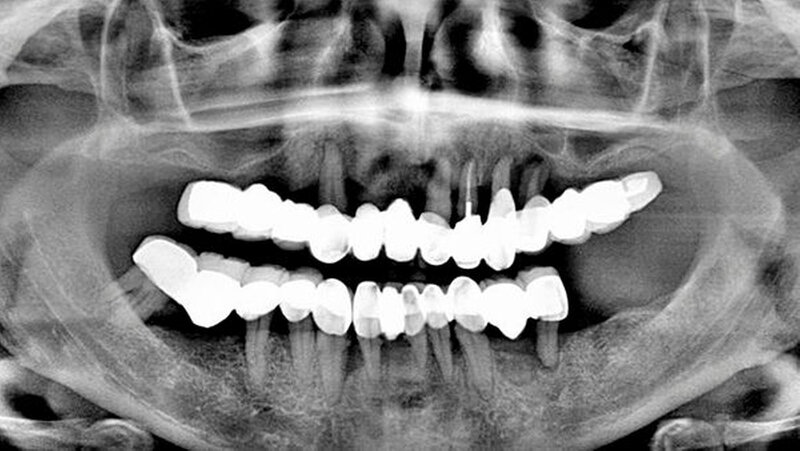

Die Patientin, 51 Jahre alt, stellte sich im April 2014 in der Praxis in Ostfildern vor. Sie ist starke Raucherin und weist eine Parodontitis marginalis profunda auf. Ihre Oberkiefer-Extensionsbrücke ist zu diesem Zeitpunkt acht Jahre alt und wurde von einem indischen Zahnarzt angefertigt, da die Frau dort einige Jahre gelebt hatte. Der Zahnersatz sei im Übrigen sehr preiswert gewesen.

Eine Parodontitistherapie ist nie erfolgt. Die Brücke hatte einen Lockerungsgrad III und musste mit allen Pfeilerzähnen entfernt werden. Die Patientin erhielt daraufhin eine Implantat-Versorgung.